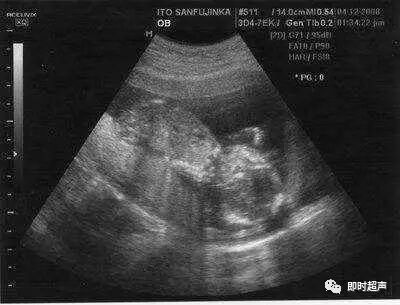

B超是产检的重要内容之一,但是有些胎儿异常是B超也是检测不出来的。几乎所有胎儿的内脏器官,在出生前都会持续不断的成长变化,因此并非在早期检查时,为正常状况的器官,就能保证在出生后也一定正常。那么,哪些胎儿缺陷B超检查不出来?下面就随小编一起来看看。

胎儿在子宫内因为没有光线的刺激,因此不会睁开眼睛,所以无法诊断出先天全盲或小眼症的状况。

6肢(指、趾)端异常

像是手脚内翻或外翻、多指(趾)、并指或指节缺失等异常状况,也因为胎儿常处于握拳状态,几乎无法由超音波确切诊断。